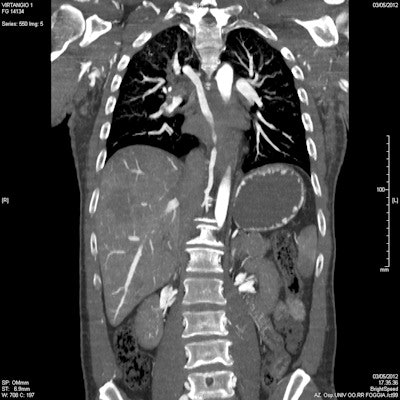

Postmortem whole-body CT angiography. Pulmonary embolism: Coronal multiplanar reconstruction (MPR) showing the filling defect in the right descending branch of the pulmonary artery."At the moment, MRI is used for very few cases because it is more difficult to use on corpses than CT, but I am sure that forensic imaging will increasingly turn to MRI to answer certain questions. It is vital that we share more knowledge about forensic imaging in general, because there is a serious lack of awareness about it," Guglielmi said.